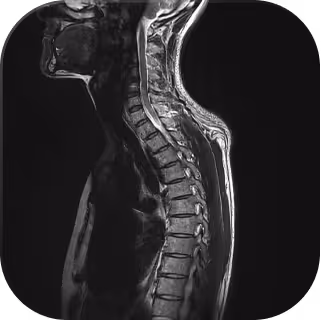

Results, you can understand.

Our digital MRI report doesn’t just give you results, it lets you explore them. Explore your own scans in detail and understand what they mean, all in one interactive view.

Each scan is reviewed by Everlab’s team of radiologists and specialist doctors, combining medical precision with preventive insight.